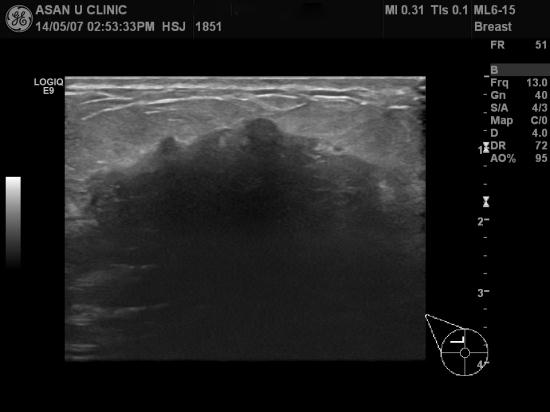

아산유외과 개원 후 100번째 유방암진단.

건강검진상 이상소견으로 의뢰된 80세 여성분입니다.

본원 유방 초음파상 좌측 유방의 상내측에 3군데의 이상소견을 보였고

조직검사상 각각 유방의 침윤성 유관암 진단되셨습니다.

가장 큰 혹이 1.6cm이었으며

겨드랑이 림프절에 전이 의심소견이 없는 것으로

조심스레 1기정도로 추정해볼 수 있으나

정확한 암의 장경, 즉 가장 긴 길이는

수술해서 떼어낸 조직을 통해 더 정확히 결절됩니다.